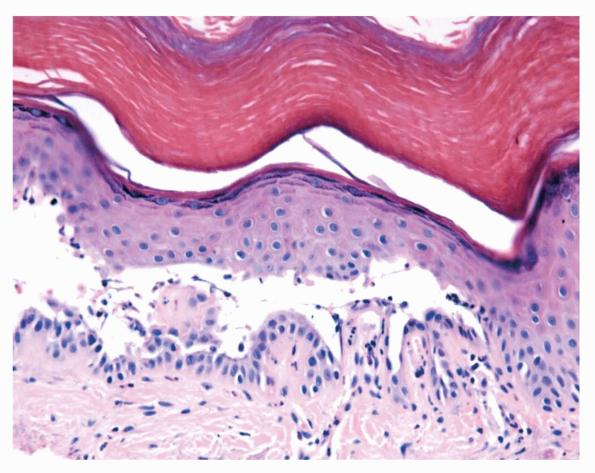

The earliest recognized change may be either eosinophilic spongiosis rarely or, more commonly, “spongiosis” in the lower epidermis . This spongiosis may actually represent the earliest manifestation of acantholysis rather than true spongiosis as defined earlier. Acantholysis leads first to the formation of clefts and then to blisters in a predominantly suprabasallocation . The intraepithelial acantholysis may extend into adnexal structures or occasionally be higher in the stratum spinosum. The basal keratinocytes, although separated from one another through the loss of attachment, remain firmly attached to the dermis like a “row of tombstones.” Within the blister cavity, the acantholytic keratinocytes, singularly or in clusters, have rounded condensed cytoplasm about an enlarged nucleus with peripherally palisaded chromatin and enlarged nucleoli. In some patients, there are varying quantities of antidesmoglein 1 and antidesmoglein 3 antibodies, leading to variable planes of acantholysis. There is little inflammation in the early phase of blister formation. If present, it is usually a sparse, lymphocytic perivascular infiltrate accompanied by dermal edema. However, if eosinophilic spongiosis is apparent, numerous eosinophils may infiltrate the dermis. The phenomenon of eosinophilic spongiosis occurs occasionally in other blistering diseases, particularly in their early phases, including acute contact dermatitis, pemphigus foliaceus, bullous pemphigoid, herpes gestation is, drug eruptions, spongiotic arthropod bite reactions, and transient acantholytic dermatosis. Several important changes ensue as the lesions age. First, a mixed inflammatory cell reaction consisting of neutrophils, lymphocytes, macrophages, and eosinophils may develop. Because of the instability of the blister roof, erosion and ulceration may occur. Older blisters may also have several layers of keratinocytes at the blister base because of keratinocyte migration and proliferation. Last, there may be considerable downward growth of epidermal strands, giving rise to so-called villi (Fig. 9-9D). The evaluation of patients with only oral lesions is difficult, because intact blisters are rarely encountered due to the trauma of mastication, and biopsies may show only erosion and ulceration. Indeed, it is best to sample the edge of a denuded area with intact mucosa in an attempt to demonstrate the typical pathologic changes. Clinicians frequently cannot distinguish between an ulcer and the intact mucosa, as both are often white and shaggy. In patients with only oral lesions, biopsies of intact oral mucosa for DIF testing are more sensitive than biopsies of lesions for routine light microscopic evaluation. Therefore, biopsy from the normal maxillary and upper buccal mucosa is necessary when there is extensive ulceration. Cytologic examination using a Tzanck preparation is useful for the rapid demonstration of acantholytic epidermal keratinocytes in the blisters of pemphigus vulgaris. For this

Differential DiagnosisIn early blisters that are free of secondary changes, such as the degeneration or regeneration of epidermal cells, the histopathology of pemphigus vulgaris is characteristic. Important differential diagnoses include Hailey-Hailey disease and transient acantholytic dermatosis. Hailey-Hailey disease has full­thickness (“dilapidated brick wall”) acantholysis, epidermal hyperplasia, and an impetiginized scale crust. The acantholysis does not extend down follicles as it does in pemphigus. Transient acantholytic dermatosis may exhibit small foci of intraepidermal acantholysis, but these are only a few rete wide in contrast to the uniform widespread acantholysis observed in biopsies of pemphigus vulgaris. Disorders such as Darier’s disease that are characterized by acantholytic dyskeratosis are readily separated from pemphigus vulgaris by the presence of abnormal granular keratinocytes and parakeratotic cells, so-called corps ronds and corps grains. Although light microscopic examination of pemphigus lesions is important, positive DIF is the gold standard in diagnosis at this time and must be pursued in all cases in which pemphigus vulgaris is considered.